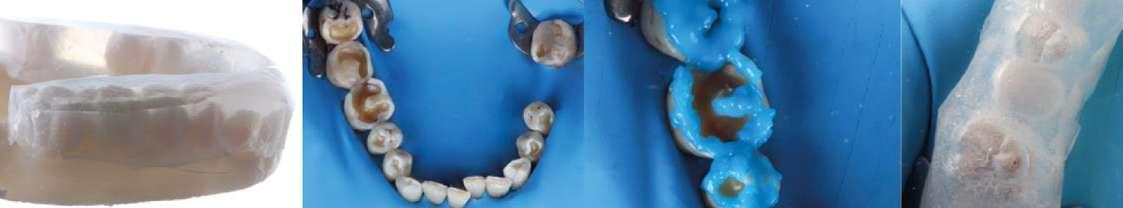

Determinación de la Dimensión Vertical en Oclusión (DVO)

Se planificó un aumento de ambas arcadas. La nueva dimensión vertical de oclusión (DVO) se determinó mediante un arco gótico y se validó con registros de movimientos laterales y protrusivos obtenidos con el sistema Zebris (Fig. 7–9). Y se procedió a realizar un CBCT con arco gótico colocado para validar la posición intermaxilar.

3. Provisionalización posterior con técnica de composite estampado y guías de silicona transparente (Fig. 10–21).

Provisionalización y planificación ortodóncica

Se decidió provisionalizar únicamente el sector posterior (Fig. 22-24), en lugar de ambos sectores (anterior y posterior), con el objetivo de facilitar el espacio necesario para los movimientos ortodóncicos y desbloquear el sector anterior, permitiendo así una mayor libertad de desplazamiento dental. El paciente fue informado previamente de que, durante la fase ortodóncica, presentaría una mordida abierta anterior y provisionales posteriores de larga duración. Asimismo, se le explicó que al finalizar el tratamiento se observarían diastemas en los incisivos superiores, consecuencia de la inclinación vestibular planificada, considerando que dichos dientes serían posteriormente restaurados. Para la colocación de los provisionales de composite se empleó un sistema adhesivo autograbante con grabado selectivo del esmalte, con el fin de evitar sensibilidad postoperatoria y lograr un sellado inmediato de la dentina, dado el grado de exposición re-

Figura 7-9. Registros tomados mediante uso de un arco gótico digitalmente diseñado junto con registro de movimientos dinámicos.

Figura 10-17. Encerado digital para guiar el tratamiento ortodóntico y restaurador.

Figura 18-21. Provisionalización con técnica de estampado.

sultante del desgaste severo. Una vez establecida la provisionalización de larga duración y determinada la nueva dimensión vertical de oclusión, se tomaron los registros necesarios para iniciar la fase de alineación ortodóncica con el sistema Invisalign Go™. Dichos registros incluyeron escaneados intraorales de ambas arcadas y una secuencia fotográfica completa obtenida mediante la aplicación Invisalign PracticeApp®.

Figura 22-24. Provisionalización solo en sector posterior.